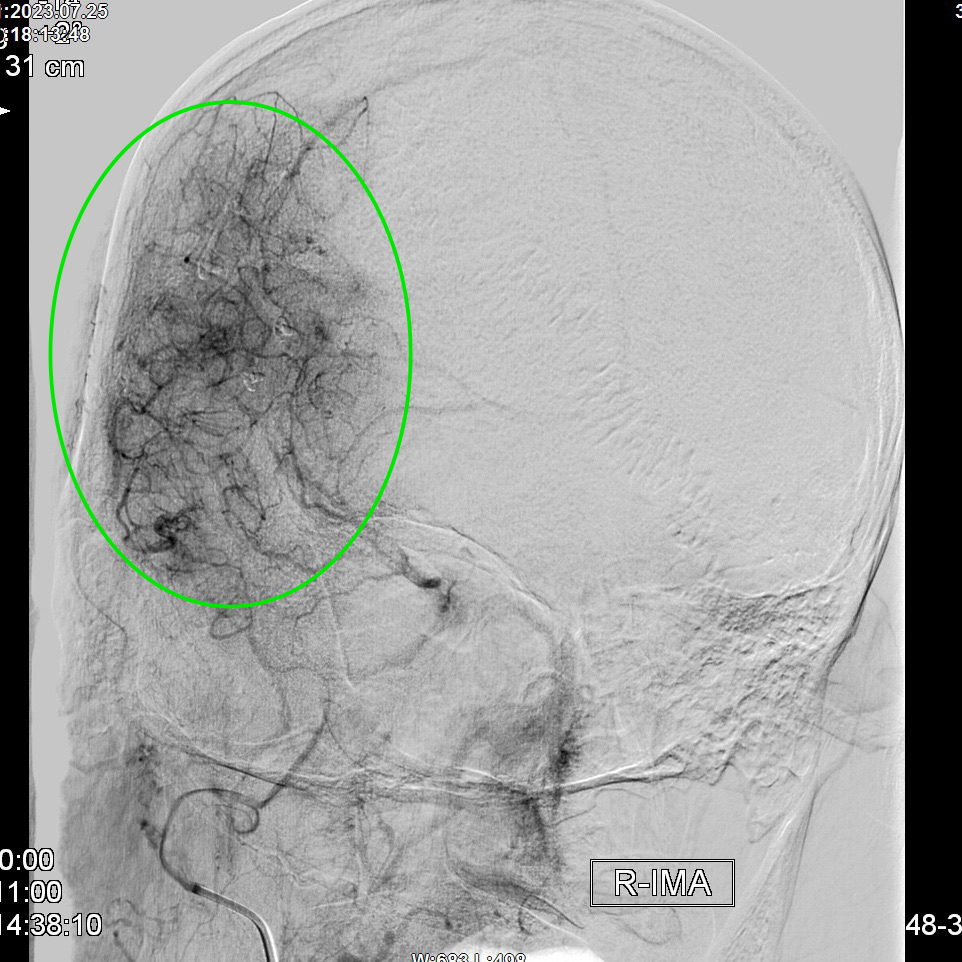

昆明三博2023:颞浅动脉一大脑中动脉M3吻合术